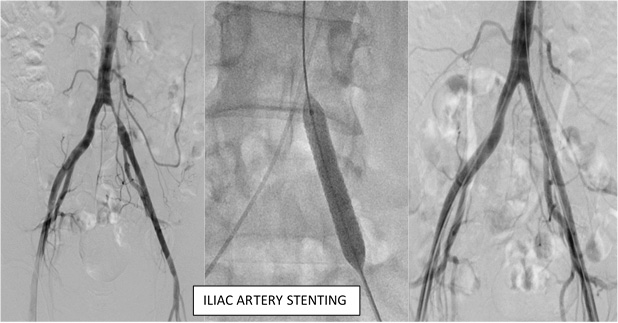

STENTING

Sometimes, following balloon angioplasty, the doctor will place a stent (a tiny mesh tube) in the artery to help keep it open. Those who receive stents will also need to be on clot-preventing medications to reduce the chance of clots forming inside the stent.